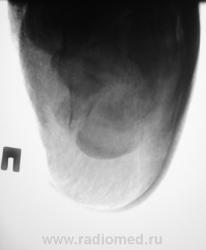

Лечение состояло из "множества рентгенов" и гипса. Срок - 5 месяцев.

Сейчас думают об остеомиелите.

Контуры пяточной кости относительно четкие, разрежение структуры пяточного бугра, в проекции перелома уплотнение структуры кости( имею в виду последние снимки).Клиника остеомиелита есть?

Во-первых, деформация пяточной кости; во-вторых, отсутствие консолидации, через некоторое время и ложный сустав сформируется. Неоднородное уплотнение костной структуры в теле кости может быть обусловдено как остеомиелитом, так и перераспределением нагрузки.

Признаков остеомиелита не вижу, только консолидир перелом с неуд стоянием отломков.